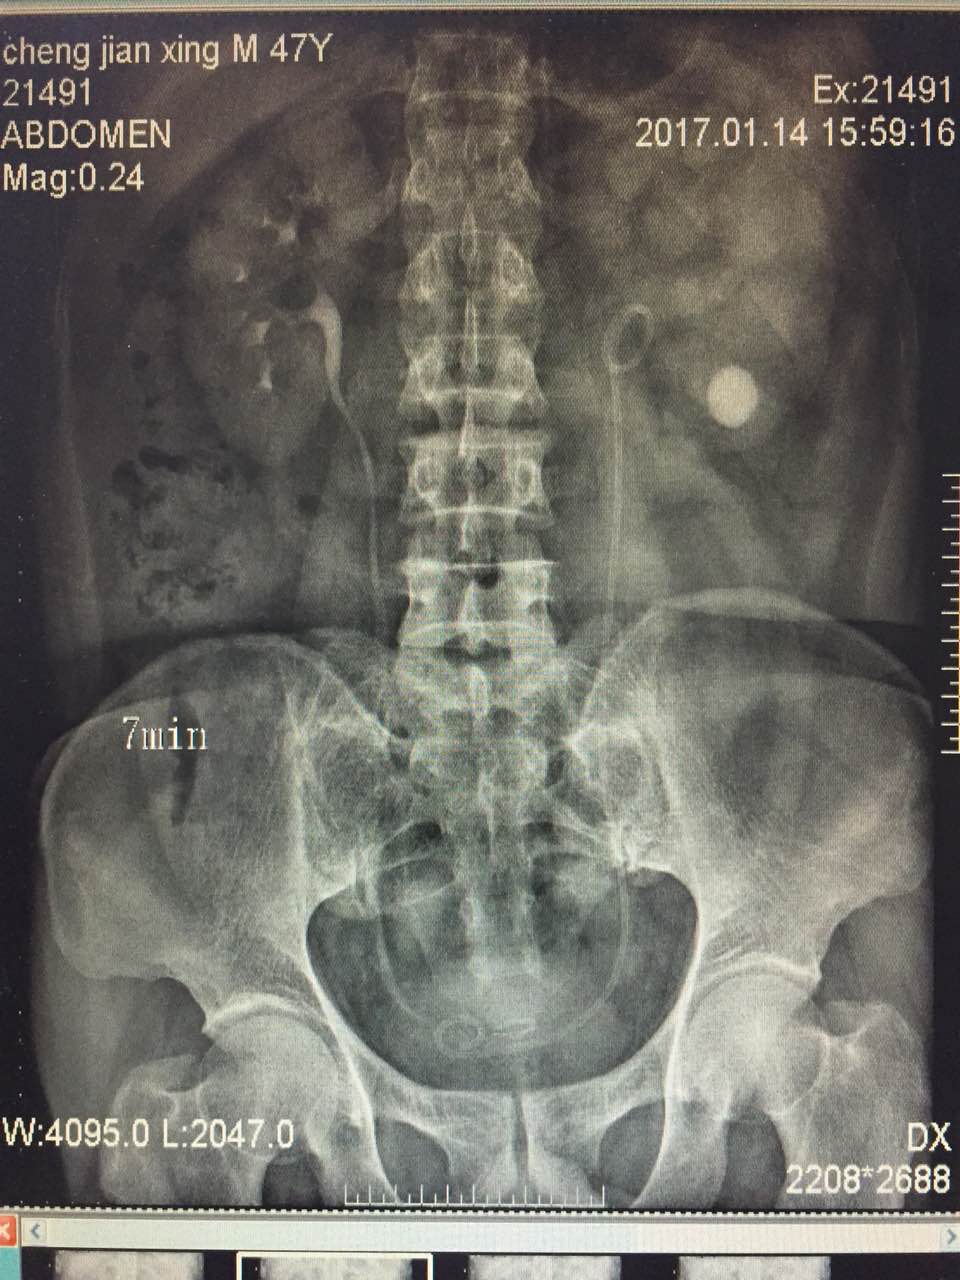

患者,男,47岁,间断性左侧腰背部疼痛不适8年,于当地医院诊断为左肾积水,左肾结石,曾行体外冲击波碎石治疗,无效,遂就诊于我院泌尿外科。完善泌尿系CT及静脉泌尿系造影后诊断为左肾积水,左侧输尿管狭窄,左肾结石,泌尿外科李朝明主任及其团队反复研究患者病情后决定行经尿道输尿管镜联合肾镜输尿管狭窄高压球囊扩张术,手术过程顺利,术后住院恢复治疗20天,目前已完全康复出院。